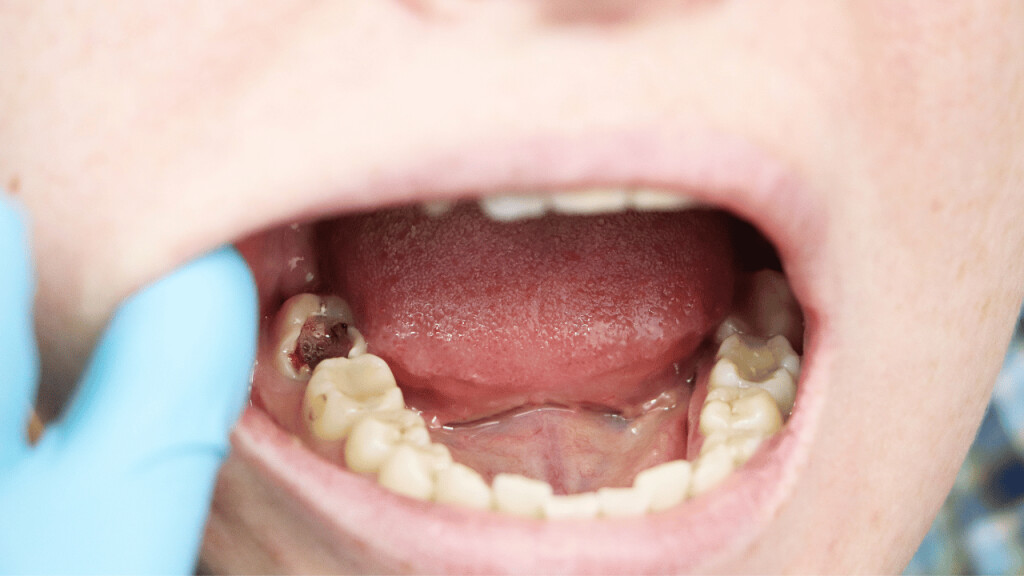

Tooth Decay

The fully impacted or the partially impacted wisdom teeth are at greater risk of tooth decay, than other teeth. This usually happens, because of the location of the wisdom tooth, especially towards the back of the mouth, which is hard to clean. Moreover, since it lies at the back of the mouth, there are chances of food getting easily trapped between the gums and the tooth, promoting the growth of bacteria.

Formation of Cysts or Tumours

If the wisdom teeth problems are not dealt in an appropriate manner, the tooth will develop a sac within the jawbone. This sac has the ability to fill with fluid, which gradually develops into the formation of cyst, damaging the teeth, jawbone, and nerves. There are chances that this cyst could progressively develop into a tumour if untreated which could ultimately result in the removal of tissue and jaw bones.

As tooth decay progresses, it can reach the softer inner layers of the tooth, called dentin and pulp, resulting in sensitivity to hot, cold, or sweet foods and drinks and eventually leading to a toothache. If left untreated, tooth decay can result in an abscess, a painful infection at the root of the tooth that can cause severe pain and swelling. Adhering to your routine dental check-ups, practicing good oral hygiene, and eating a healthy diet can help prevent tooth decay and the resulting toothache.

Abscessed tooth

An abscessed tooth occurs when the pulp inside your tooth becomes infected, typically due to decay or damage. The infection can spread to the tooth’s root and surrounding tissues, causing pain and swelling. In some cases, a pocket of pus may form in the affected area, leading to additional discomfort and even fever. Abscessed teeth may also cause sensitivity to hot or cold foods, a bad taste in your mouth, and difficulty chewing or speaking. If you have an abscessed tooth, inform your provider to prevent further complications and potential tooth loss.